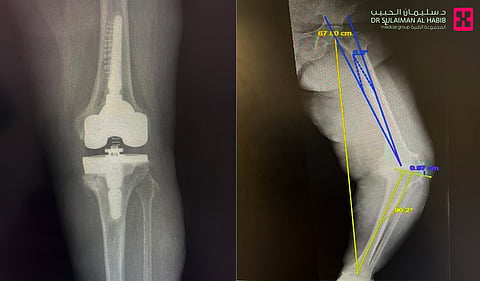

وأشار الدكتور سكيك؛ إلى أن نتائج الفحوصات المخبرية وأشعة (Digital X-Ray) والرنين المغناطيسي (M.R.I) أثبتت وجود خشونة شديدة من الدرجة المتقدمة، فضلاً عن تقوس حاد بالركبة اليسرى أدّى إلى ضعف العصب وبالتالي عدم قدرتها على فرد الساق أو رفعها لأعلى، إضافة إلى إصابتها بهشاشة العظام وتآكلٍ شديدٍ في عظام أسفل المفصل، وبعد إجراء دراسة دقيقة للنتائج كافة، قرّر الفريق الطبي التدخل جراحياً.

وقال استشاري جراحة العظام إنه بعد استكمال الفحوصات الطبية واتخاذ الترتيبات اللازمة، أُجريت للمريضة عملية جراحية دقيقة استغرقت 3 ساعات متواصلة تحت التخدير الجزئي، وتمّ فيها معالجة التقوس، ومن ثم استبدال المفصل بآخر جديد من مادة "التيتانيوم" الذي يتيح سلاسة الحركة والعمر الطويل من الاستخدام، علاوة على تعويض تآكل العظام بوضع دعامات خاصة من مادة "التانتيلوم".